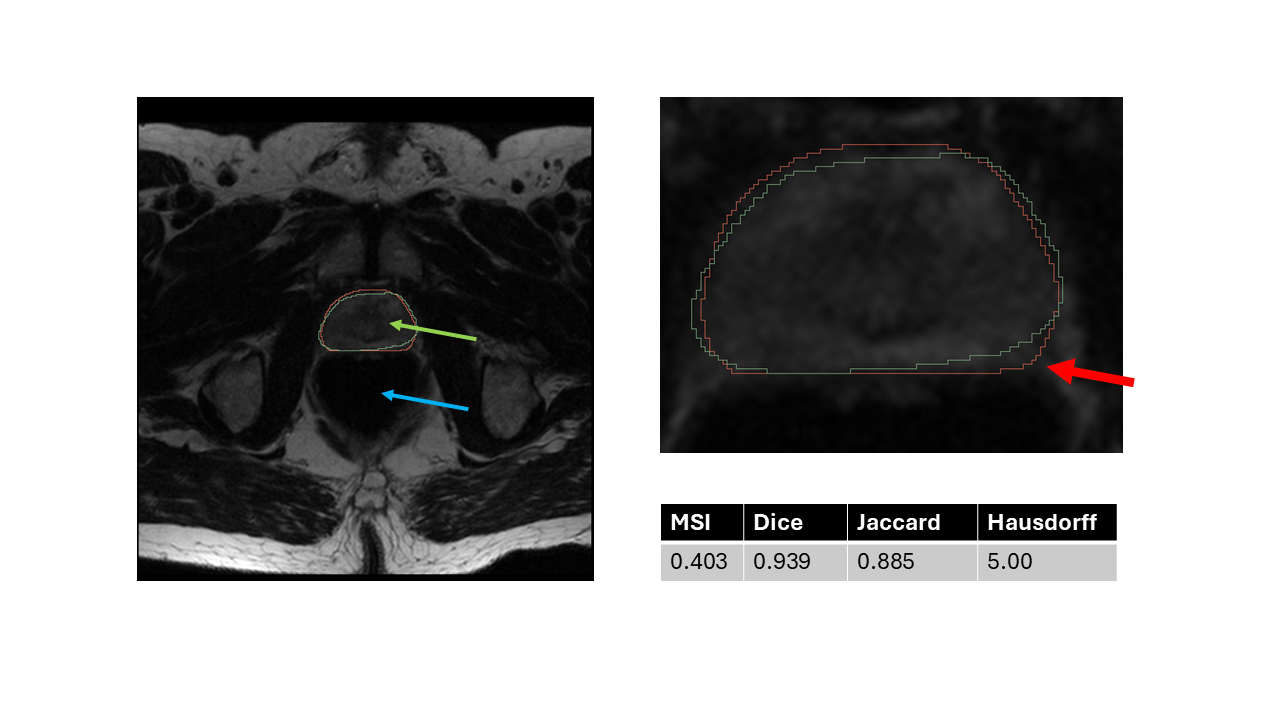

The impact of the outer deviation is crucial in the current clinical application, that is why we need the desired metric to represent the segmentation defects which lays out of the reference segmentation. This phenomenon can be nicely studied in the following case. In Fig. 13 we represent one slice of one test segmentation, where the outer segmentation deviation reaches the urinary bladder. In this case the segmentation is unacceptable. The traditional metrics and the value of MSI with il=1\texttt{il}=1, ol=10\texttt{ol}=10. The Dice (0.939) and Jaccard score (0.886) show high values, the Hausdorff distance show a medium value (5.0), while the MSI (0.403) has a very low value. Only the MSI characterizes the segmentation correctly. The metric values considering all slices and the masks are presented in Appendix (see Fig. A1).

Refer to caption

Figure 13: Representative test slice with crucial outer deviation of the test segmentation. The reference segmentation is show in green, the neural network predicted segmentation is shown in red. The predicted segmentation has an outer deviation, which reaches in the urinary bladder. In case of radiotherapy, this deviation would have serious effects, so the segmentation is unacceptable, which is only indicated by the MSI metric (all the traditional metrics show good values). The MSI value was calculated using il=1\texttt{il}=1, ol=10\texttt{ol}=10 hyperparameters. The urinary bladder is indicated by green arrow, the prostate is indicated by blue arrow in the T2W MRI images.

slice index MSI Dice Jaccard Hausdorff

6 0.205179 0.922558 0.856248 5.385165

7 0.403701 0.939892 0.886601 5.000000

8 0.416621 0.951325 0.907168 5.656854

9 0.686597 0.949580 0.904000 8.485281

10 0.727526 0.961066 0.925051 4.000000

11 0.619143 0.977774 0.956514 3.000000

12 0.730977 0.937705 0.882716 9.000000

13 0.596483 0.972026 0.945574 3.605551

14 0.767887 0.970246 0.942211 5.385165

15 0.671288 0.953519 0.911167 7.280110

16 0.254589 0.922909 0.856854 7.071068

17 0.732791 0.957405 0.918290 4.242641

18 0.634041 0.895528 0.810820 13.892444

19 0.551165 0.835125 0.716923 5.830952

20 0.567933 0.048998 0.025114 14.212670

Table 2: The MSI values for the slices shown in Fig. A1. The MSI values were calculated with il=1\texttt{il}=1, ol=10\texttt{ol}=10 hyperparameters.